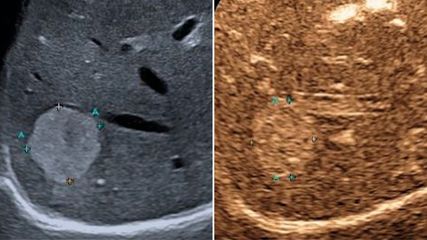

Fokale Leberläsionen sind nicht nur in der Gastroenterologie und Hepatologie, sondern auch in der internistischen und hausärztlichen Praxis ein häufiger Befund bei CT-, MRT- oder ...